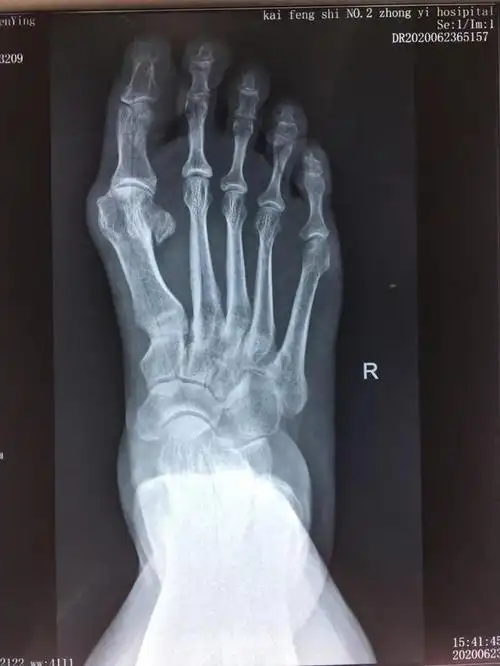

36岁双足拇外翻畸形矫正手术一例

x光片更直观了解大脚骨 如果单纯去掉凸起能否有效矫正拇外翻呢?

负重x线片观察:第一二跖骨间夹角增大明显,第二跖趾关节半脱位.